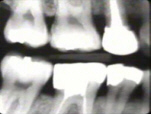

La Radiografía del lado

derecho muestra pérdida moderada del hueso periodontal con una tendencia

de bolsas infraóseas en los primeros premolares superiores.

|

La radiografía del

lado izquierdo revela pérdida moderada de hueso periodontal.

La radiografía periapical muestra al cuadrante superior derecho,

en particular

al premolar, una bolsa infraósea en mesial y distal |